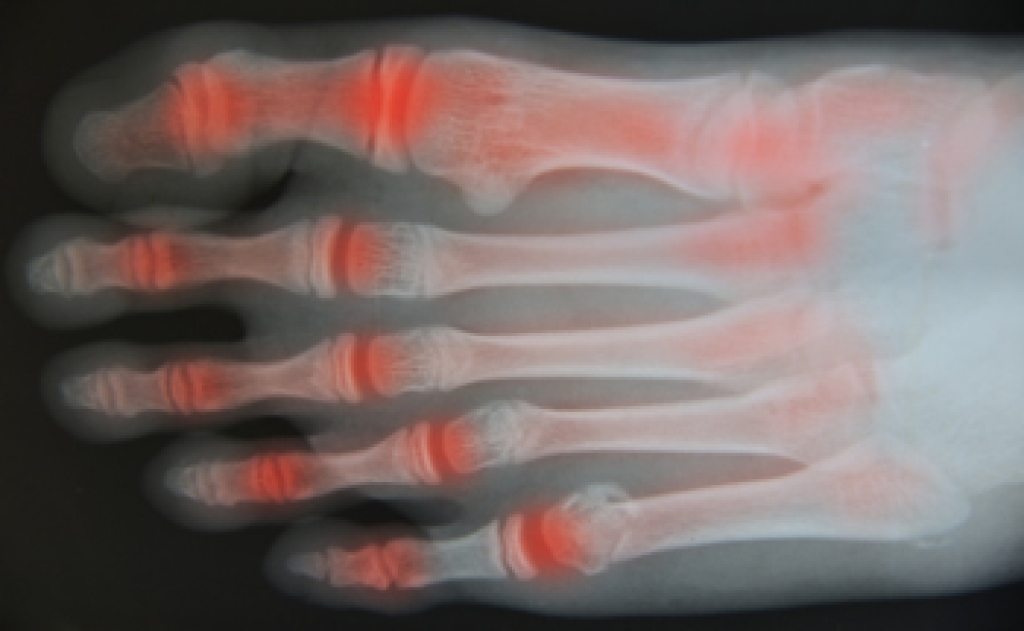

When it comes to foot pain, it's important to recognize that it can be more than just a temporary inconvenience. In fact, in many cases, foot pain might be an early sign of arthritis. This widespread condition affects millions of people worldwide, and it can have a profound effect on various joints throughout the body, including those in the feet. One of the most prevalent forms of arthritis that affects the feet is osteoarthritis. This condition develops as the cartilage cushioning the joints wears down over time, leading to persistent pain, stiffness, and swelling. Another type, rheumatoid arthritis, is an autoimmune disorder that can also target the foot joints, resulting in discomfort and deformities. It is important not to ignore foot pain, as it might be your body's early warning signal for an underlying arthritis condition. If you're experiencing persistent foot pain, especially in the morning or after periods of inactivity, it's suggested that you make an appointment with a podiatrist for a comprehensive examination, necessary diagnostic tests, and a tailored treatment plan to manage your symptoms effectively.

Arthritis is a term that is commonly used to describe joint pain. The condition itself can occur to anyone of any age, race, or gender, and there are over 100 types of it. Nevertheless, arthritis is more commonly found in women compared to men, and it is also more prevalent in those who are overweight. The causes of arthritis vary depending on which type of arthritis you have. Osteoarthritis for example, is often caused by injury, while rheumatoid arthritis is caused by a misdirected immune system.

Arthritic symptoms range in severity, and they may come and go. Some symptoms stay the same for several years but could potentially get worse with time. Severe cases of arthritis can prevent its sufferers from performing daily activities and make walking difficult.